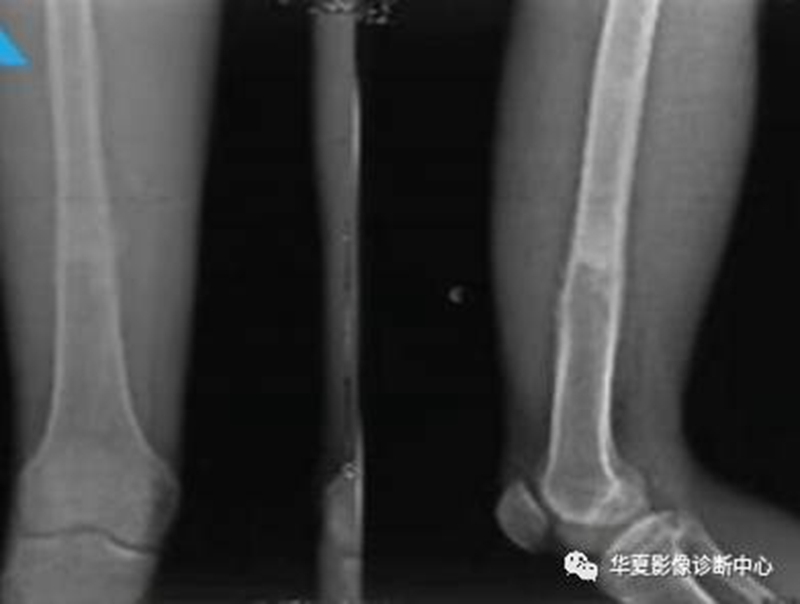

6、软组织改变

良性受压推移,恶性软组织肿块。(如下图)